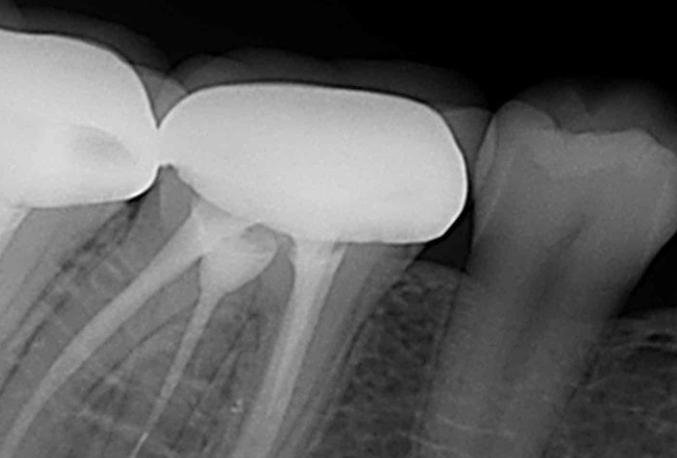

1. Image Quality and Resolution

High-quality images are critical for accurate diagnosis. Look for:

- High frequency (60–70 kHz) generators

- Digital sensor compatibility

- Adjustable exposure settings